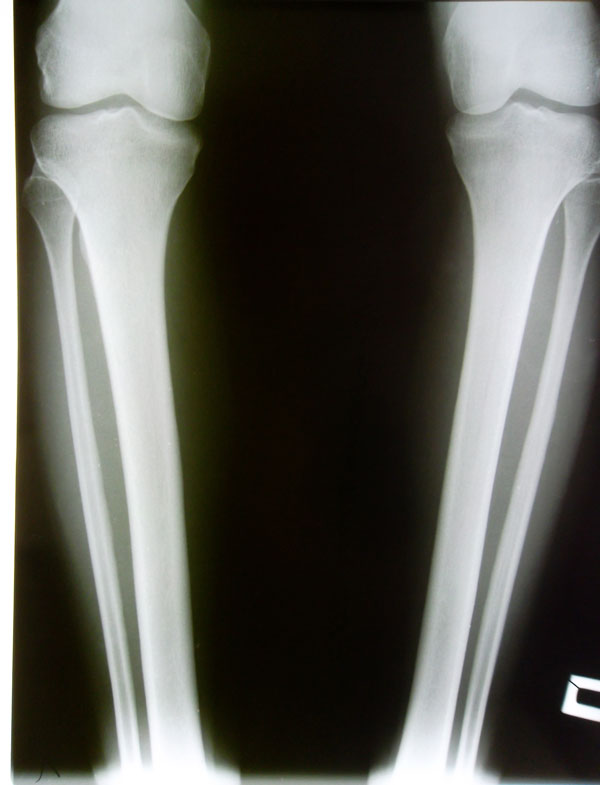

Рентгеновские снимки в прямой проекции.